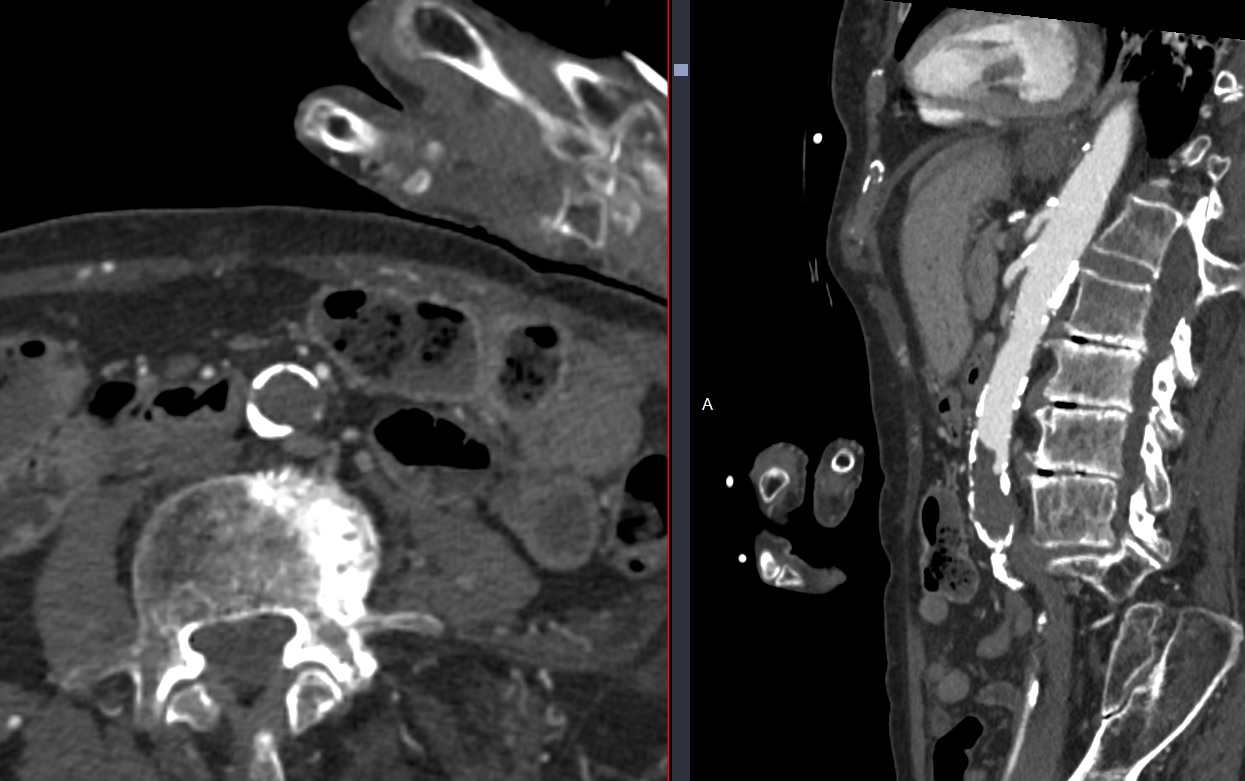

Cas

lereiche lerieche fontaine aorte aortique thrombus embol embolie occlusion iam syndrome lereiche